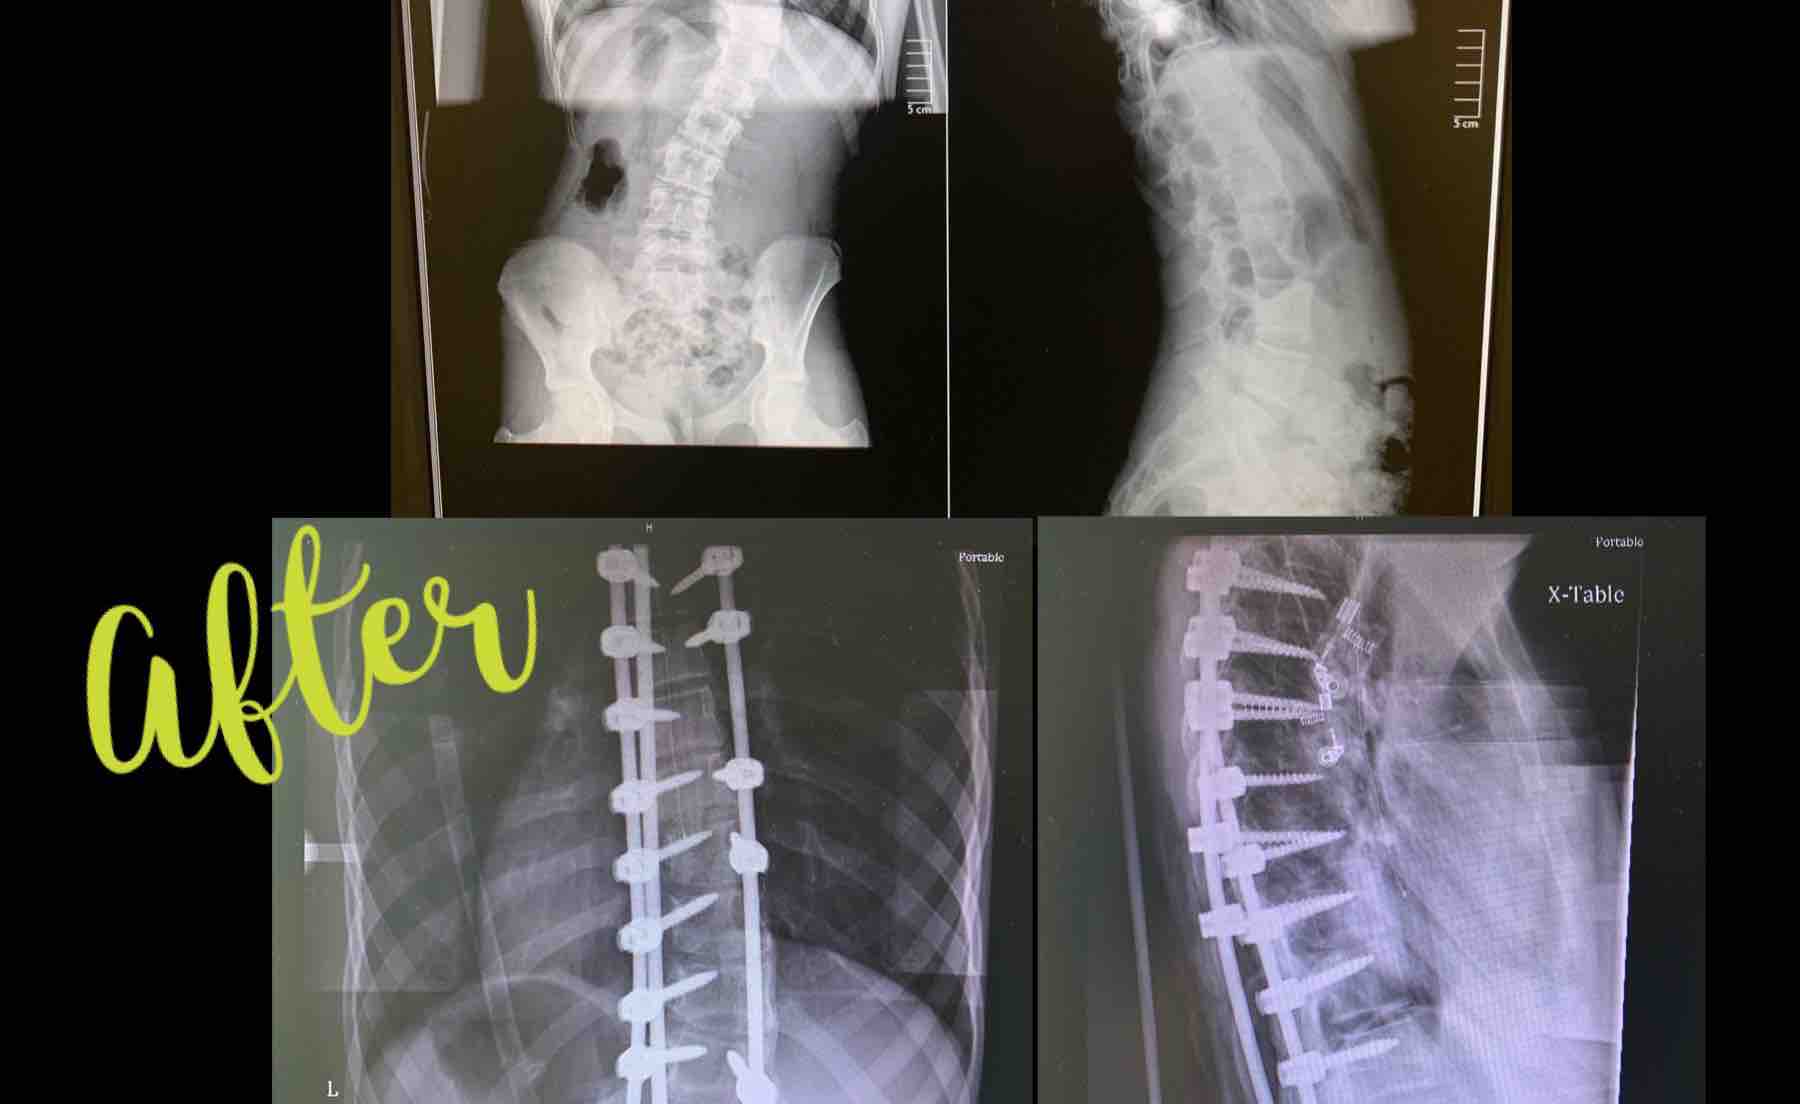

Here we are, just a year after we found out Justice has Scoliosis. We tried chiropractic care but her curvature has increased over 10 degrees in the last year and her specialist said it isn't going to stop. She is past the point for wearing a brace too. She is in pain all the time. Sometimes with a smile on her face and doing things the other kids are doing because she doesn't want to miss out. But still in pain. We have decided to proceed with back surgery. She has decided she wants to do this. It's major. It's a long recovery. She has done her homework on it, most would be scared to even know what this surgery entails. The specialist said her spine is flexible, which is great, that will allow him the best chance to get her as straight as possible.

The surgery is over 5 hours long, with a 3 day stay in the hospital and 6 weeks at home for recovery, so she will not be able to go back to school this semester. Then it's a 6 month recovery for her spine to heel. There will be good days and for sure some bad ones.